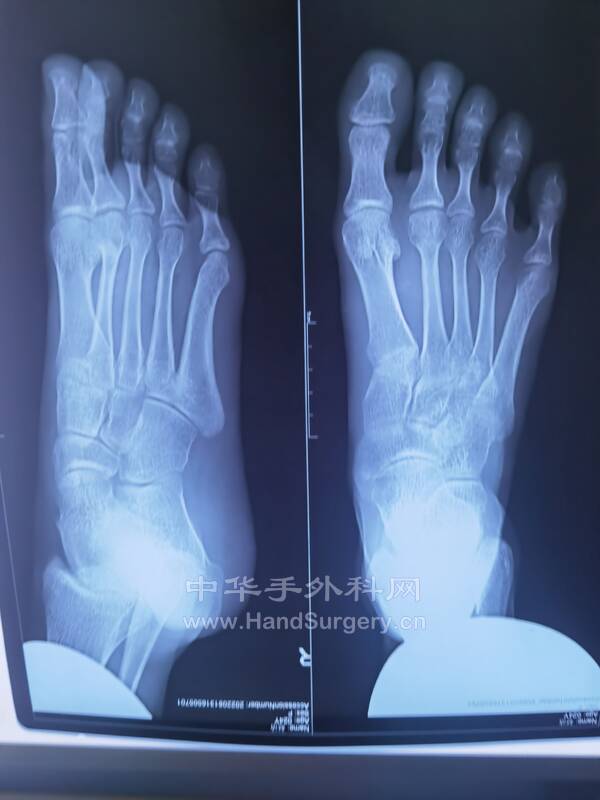

跟距骨桥,拇外翻患者行距下关节融合术,拇外翻矫形术后8周复查,